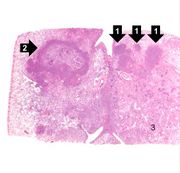

| 04:15, 19 August 2013 | IPLab3ChronicPepticUlcer3.jpg (file) | 31 KB | Seung Park | This is a low-power photomicrograph of the transected ulcer. The blue cells on the right hand side of this section are the normal gastric epithelial cells of the mucosa (1). Note the absence of any epithelial cells within the crater of the ulcer (2). | 1 | |